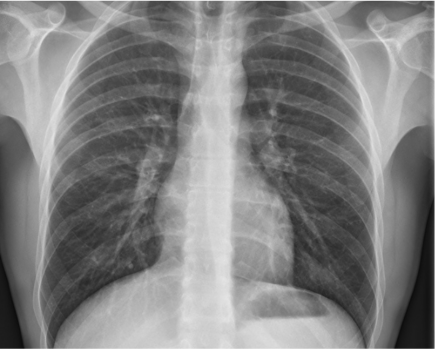

Dans une intéressante revue publiée en mars 2025 dans Investigative Radiology, une équipe coréenne nous fait un inventaire « à la Prévert » des évolutions et innovations attendues dans les 5 à 10 ans en imagerie thoracique.

D’autres points significatifs sont mentionnés dans l’article, qui présente également quelques illustrations parlantes.